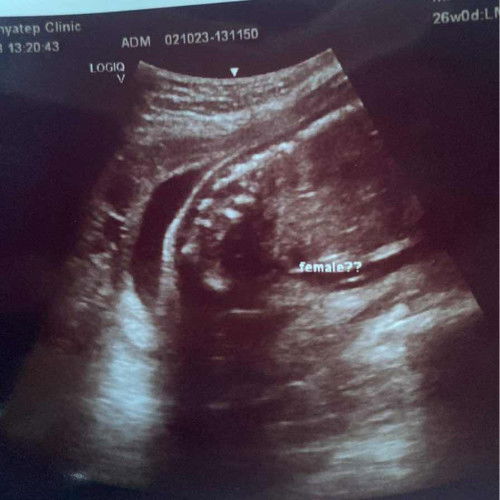

ช่วยดูให้หน่อยค่ะเพศอะไร

#ขอคำแนะนำหน่อยค่ะ #ขอบคุณสำหรับคำตอบค่ะ

Answered 2y ago by mamanotte

ไม่แน่ใจนะคะแต่จากภาพขึ้นคำว่า female ฟีเมล แปลว่าผู้หญิงค่ะ จริงๆมุมนี้เป็นเราดูไม่ออกเลยค่ะ